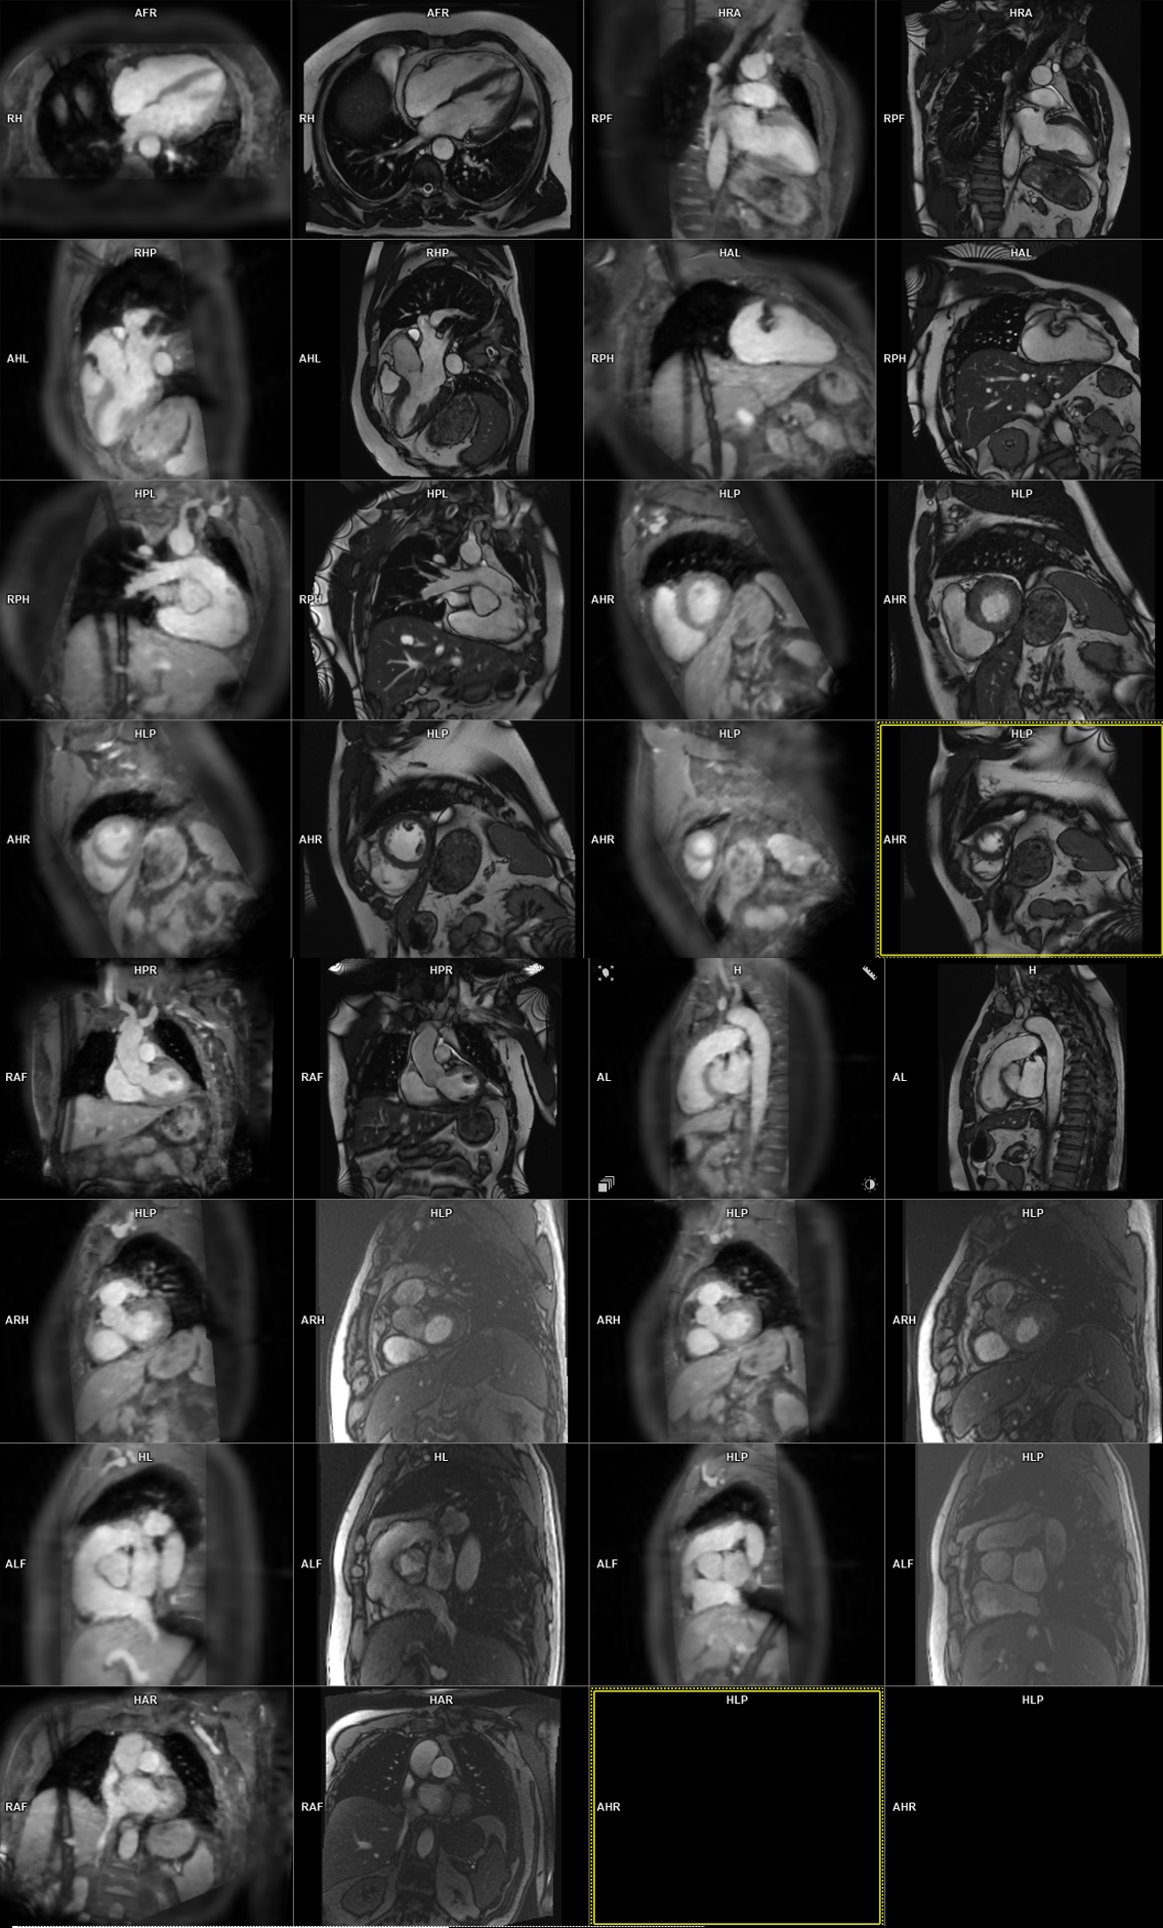

| 2.0 mm3 | 1.8 mm3 | 1.2 mm3 | ||||

| Acquisition time [min:sec] | 0:14 ± 0:03 | 1:49 ± 0:32 | 6:18 ± 1:34 | |||

| Reconstruction time [min:sec] | 0:44 ± 0:01 | 0:42 ± 0:01 | 1:40 ± 0:03 | |||

| AI detection time [min:sec] | 0:17 ± 0:02 | 0:19 ± 0:03 | 0:26 ± 0:04 | |||

| Mean Likert scores | p | Weighted kappa | Percent agreement | |||

| LV 4-chamber | 1.58 | 1.92 | 1.17 | 0.02 | 0.48 | 83 |

| LV 2-chamber | 1.67 | 2.0 | 2.0 | 0.02 | 0.21 | 92 |

| LV 3-chamber | 1.67 | 1.67 | 1.67 | 0.87 | 0.65 | 92 |

| LVOT | 1.75 | 2.0 | 2.0 | 0.05 | 0.47 | 97 |

| Short-axis | 2.0 | 2.0 | 2.0 | - | - | 100 |

| RV 2-chamber | 1.83 | 2.0 | 1.75 | 0.26 | 0.34 | 89 |

| RV 3-chamber | 1.83 | 2.0 | 1.67 | 0.37 | 0.52 | 94 |

| RVOT | 1.92 | 2.0 | 2.0 | 0.37 | 0.07 | 94 |

| Tricuspid valve | 1.42 | 1.33 | 1.50 | 0.74 | 0.1 | 92 |

| Mitral valve | 2.0 | 1.58 | 1.75 | 0.09 | 0.1 | 100 |

| Aortic valve | 1.83 | 1.58 | 1.67 | 0.37 | 0.24 | 100 |

| Above aortic valve | 1.42 | 1.92 | 1.75 | 0.07 | - | 97 |

| Pulmonary flow | 1.42 | 1.42 | 1.50 | 0.90 | 0.02 | 97 |

| Mean of all views | 1.72 | 1.80 | 1.73 | |||